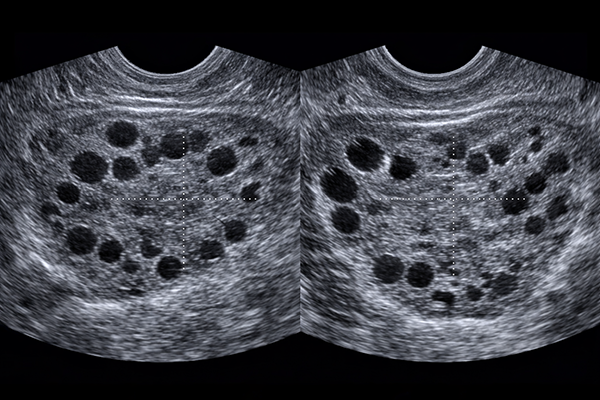

Ovarele micropolichistice reprezintă o caracteristică anatomică în care ovarele conțin un număr crescut de foliculi mici, de obicei între 12 și 25 per ovar, cu o dimensiune de aproximativ 2-9 milimetri. Acești foliculi apar ca mici structuri chistice dispuse periferic, oferind ovarului un aspect specific la examinarea ecografică. Prezența acestor structuri nu constituie în sine o boală, ci poate fi un indicator al unei tulburări hormonale mai complexe.

- Ecografia transvaginală: Ecografia transvaginală reprezintă investigația imagistică de elecție pentru evaluarea morfologiei ovariene. Această examinare permite vizualizarea detaliată a structurii ovarelor, identificând prezența a 12 sau mai mulți foliculi cu diametrul de 2-9 milimetri în fiecare ovar, sau un volum ovarian crescut peste 10 centimetri cubi.

Aspectul caracteristic prezintă foliculi dispuși periferic, conferind ovarului o aparență de "șirag de perle". Este important de menționat că acest aspect ecografic poate fi prezent și la femei fără sindrom, motiv pentru care diagnosticul nu se bazează exclusiv pe această investigație. Această abordare diagnostică comprehensivă permite medicului să stabilească un diagnostic precis și să dezvolte un plan terapeutic personalizat, adaptat nevoilor specifice ale fiecărei paciente. Odată stabilit diagnosticul, care sunt opțiunile terapeutice disponibile?